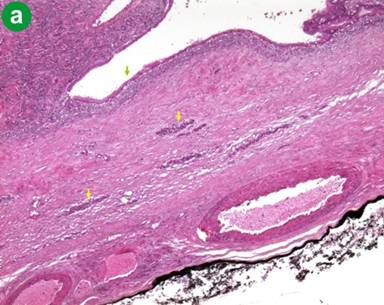

With these findings, because the patient had no a history of pancreatitis and considering the age, the sex and the imaging characteristics, a presumptive diagnosis of cystic neoplasm of the pancreas was made and a first hypothesis of a mucinous cystadenoma of the pancreatic tail was performed. A distal pancreatectomy with total splenectomy was performed. On gross inspection the pancreatic tail hosted a cyst with a smooth surface, 9 cm of maximum diameter, bilocular, containing a brownish liquid; furthermore, the lesion was adherent to the splenic capsule. Microscopically a fibrous cystic wall lined by a monolayer of cuboid epithelial cells without evidence of malignancy allowing the diagnosis of true pancreatic cyst (Figure 5). The post-operative course was uneventful and the patient was discharged 7 days after surgery; at 3-year follow-up, the patient is alive without evidence of recurrence.

Figure 5. a. Fibrous wall of the pancreatic cyst lined by cuboidal epithelium monolayer (green arrow) with trapped Langerhans islets (yellow arrows) (H&E, 10x); b. Cross section compared to the septum of the cyst (H&E, 1x).